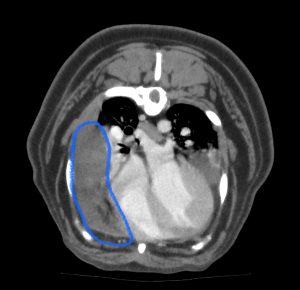

こんにちは、獣医師の松田です。今回は会陰ヘルニアのワンちゃんについてです。 会陰ヘルニアの発生にはアンドロゲン…]]>

こんにちは、獣医師の松田です。今回は会陰ヘルニアのワンちゃんについてです。 会陰ヘルニアの発生にはアンドロゲン…]]>